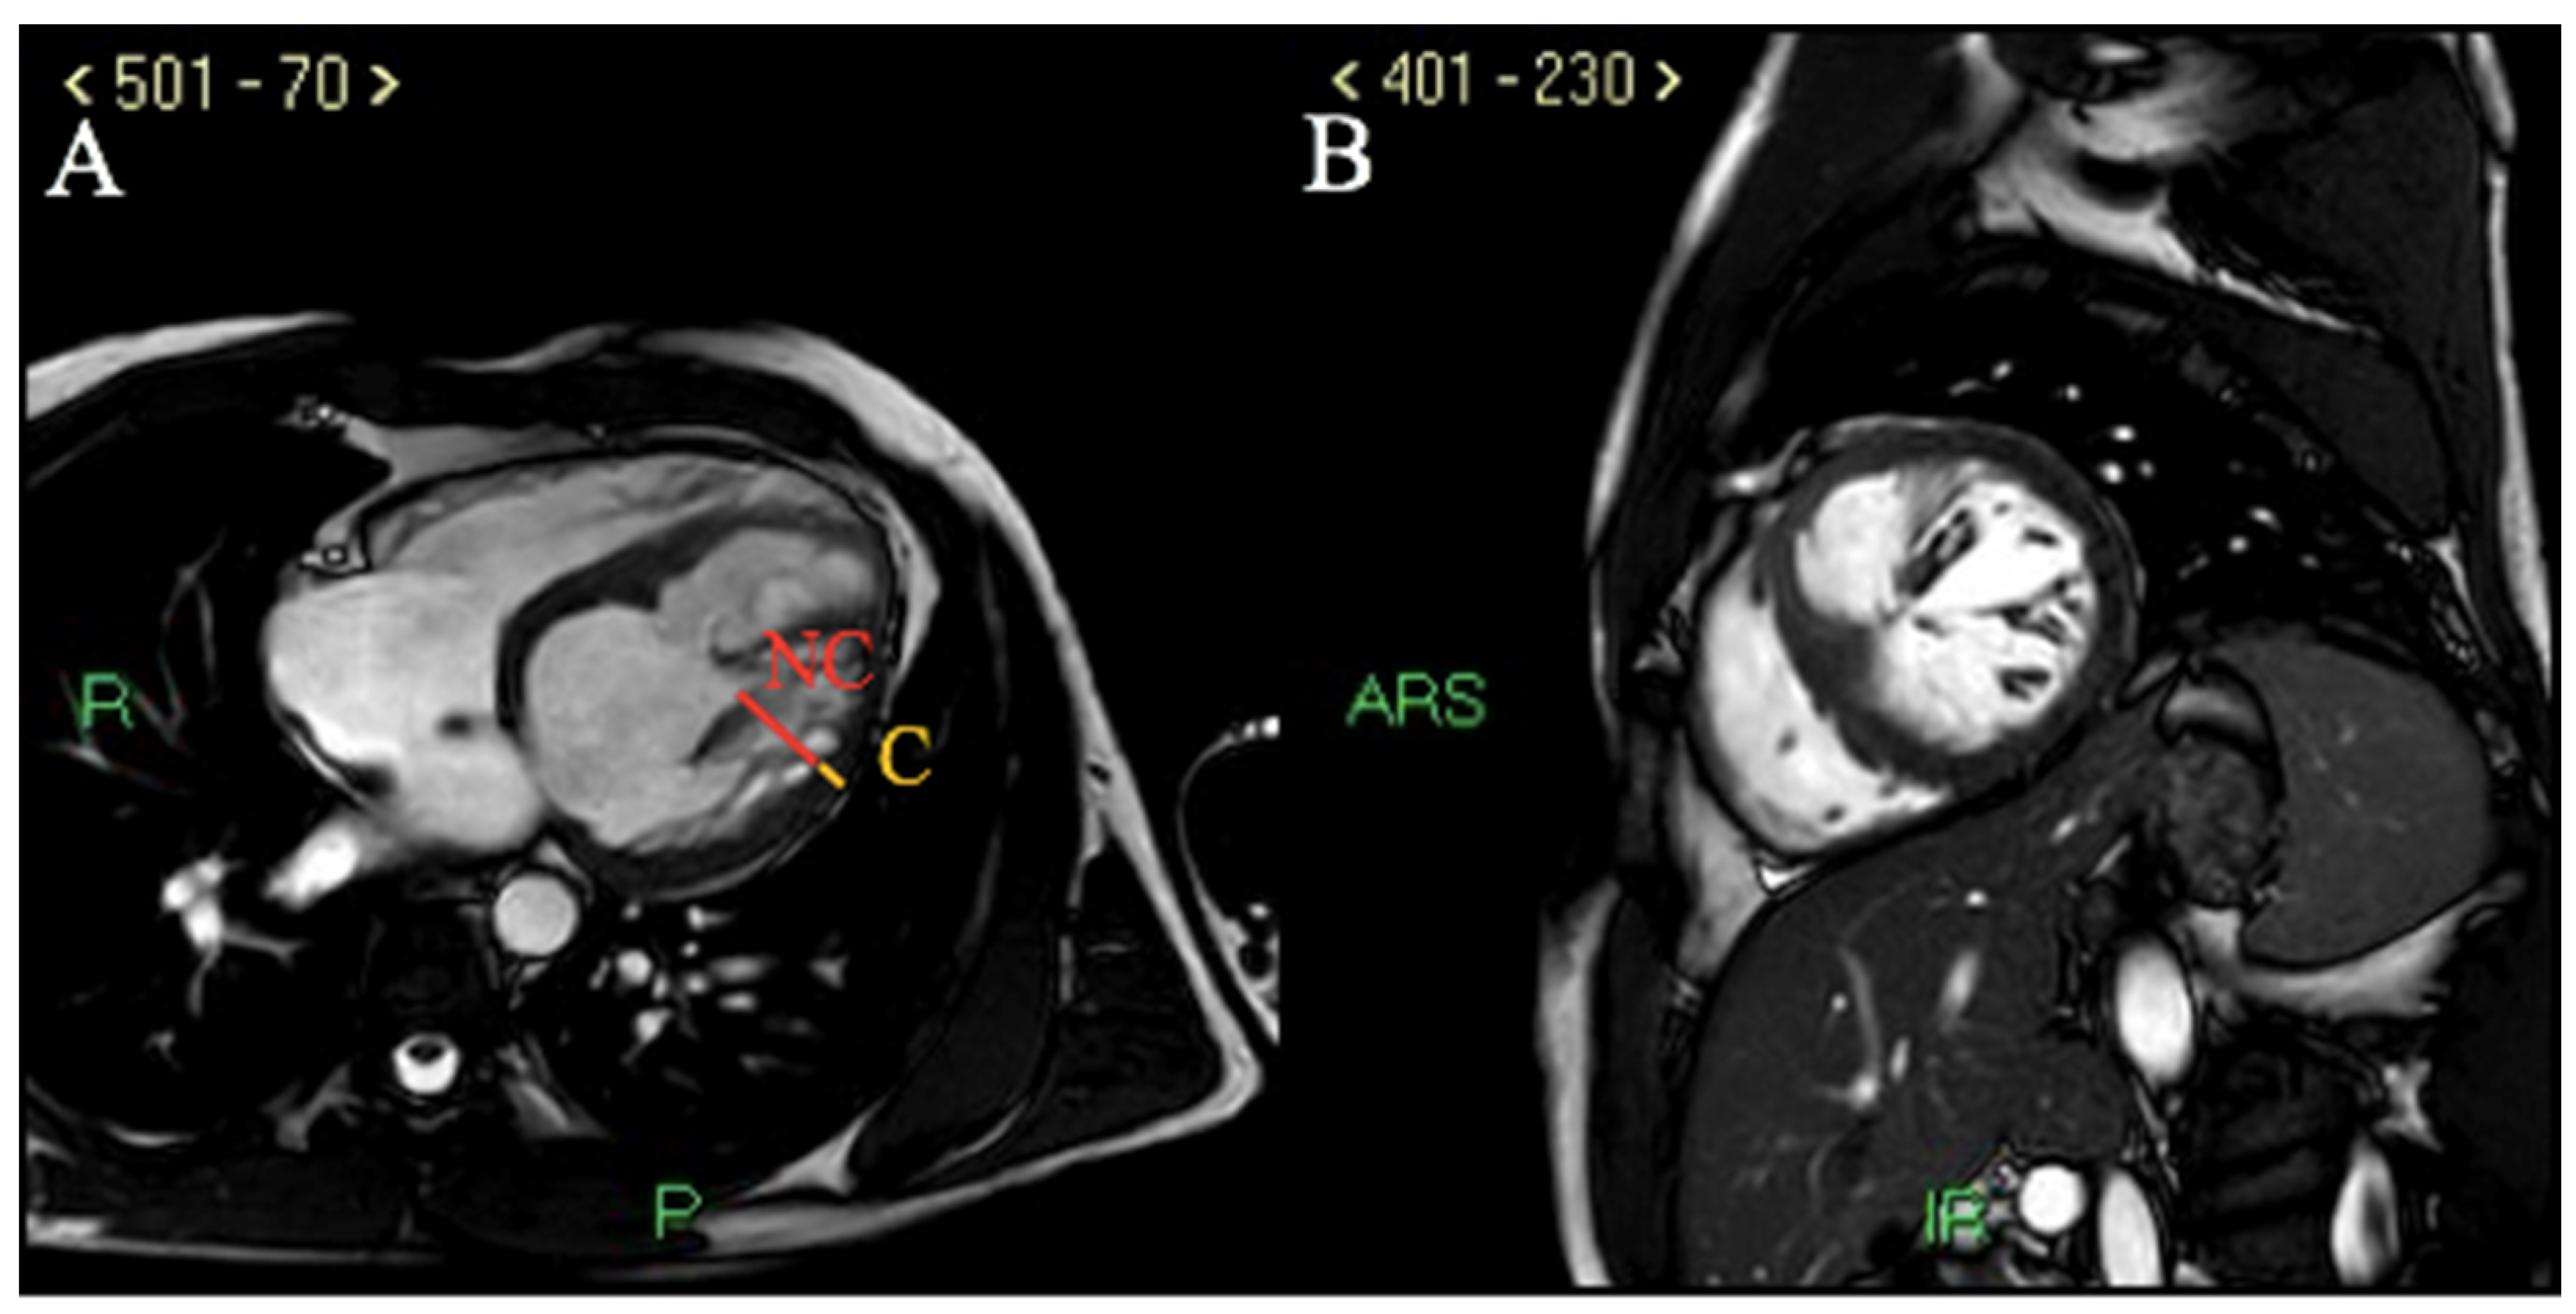

Cardiac MRI documented dilated LV with ejection fraction (EF) 34%, anterior and antero-septal wall akinesis (associated with increased T1 mapping values and areas of late gadolinium enhancement or LGE after contrast injection, compatible with ischemic pattern), infero-lateral wall hypokinesia and LV free wall marked hypertrabecularization with a telediastolic NC/C ratio of 5 in long-axis view (Figure 4A,B).

Figure 4.

Cardiac MRI. (A) cine-steady state-free precession sequence (SSFP) showing an end diastolic NC/C ratio of 5 in long axis view, diagnostic for pathologic LVNC according to Petersen’s criteria. (B) cine-SSFP sequence showing non-compaction myocardial hypertrabecularization in end diastolic short axis view.